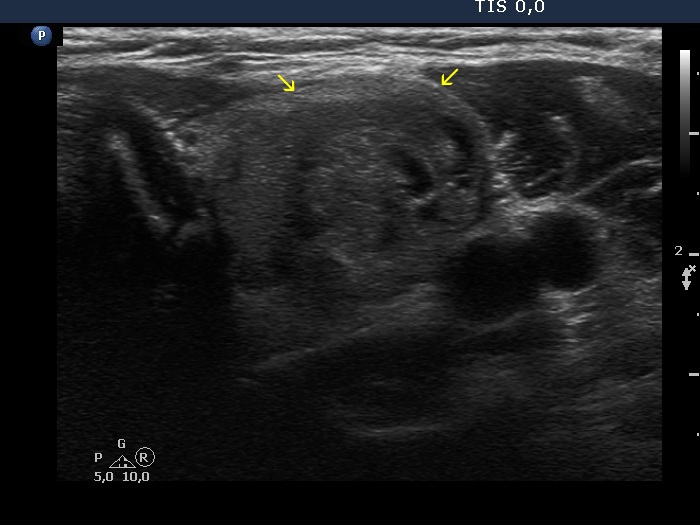

Left lobe, another transverse scan. There are several protrusions in the ventral surface of the lesion.